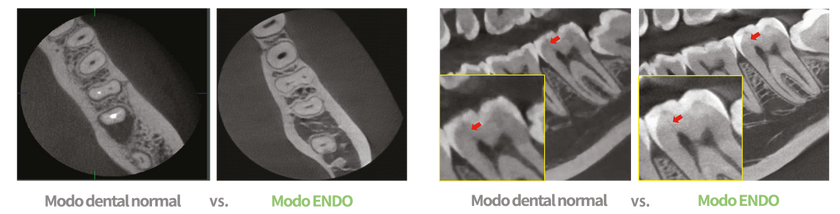

MODO ENDO DE ALTA RESOLUCIÓN

Con su FOV de 4×4 y el tamaño de vóxel de 50 micras, el modo endo optimiza el tratamiento en regiones de interés altamente enfocadas. Es ideal para uso en endodoncia porque el dentista puede lograr una imagen extraordinaria

en un tamaño de vóxel de alta resolución.